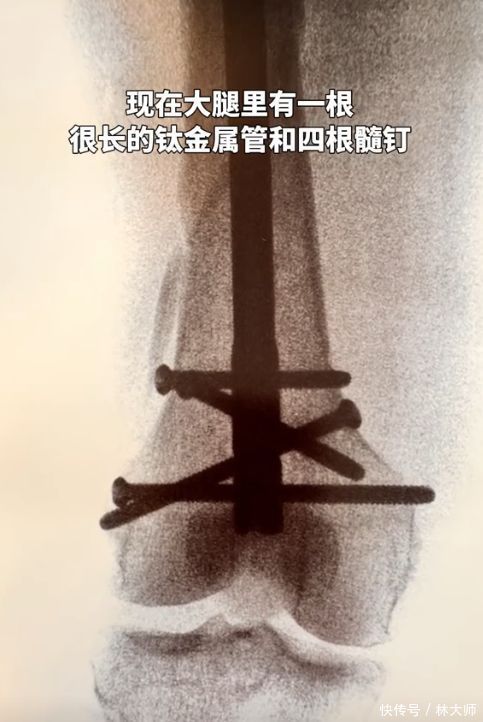

第二天私东谈主医师来家里,把向太固定在担架上,送到了病院。向太的大腿骨断裂很严重,仍是严重错位,需要立即手术,而因为伤势严重,手术足足进行了5个半小时。向太的大腿受骗今全是钢钉,伤筋动骨一百天,这些钢钉需要好几个月智商破除。